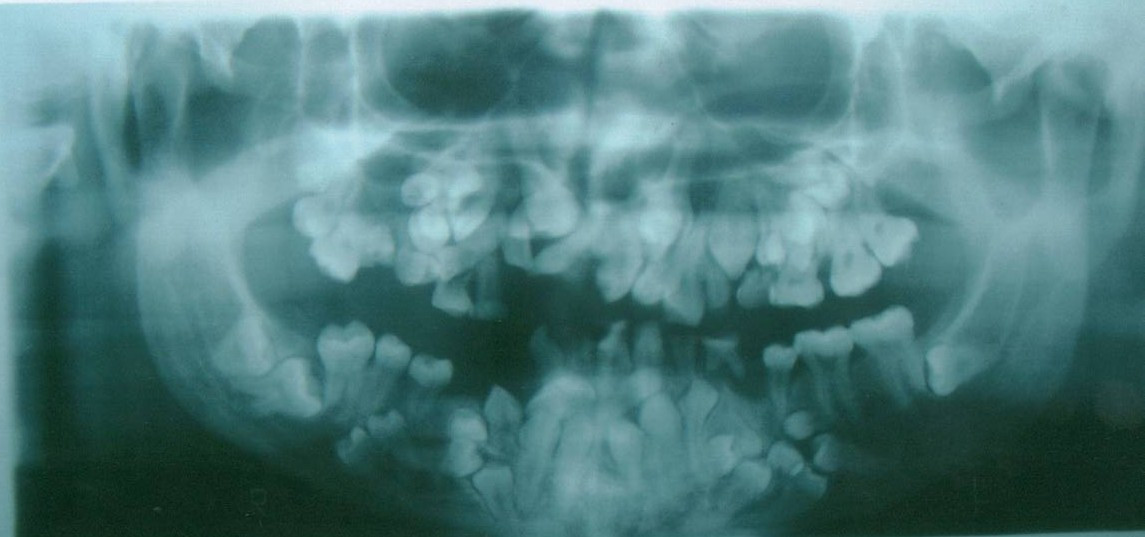

Image: 1.